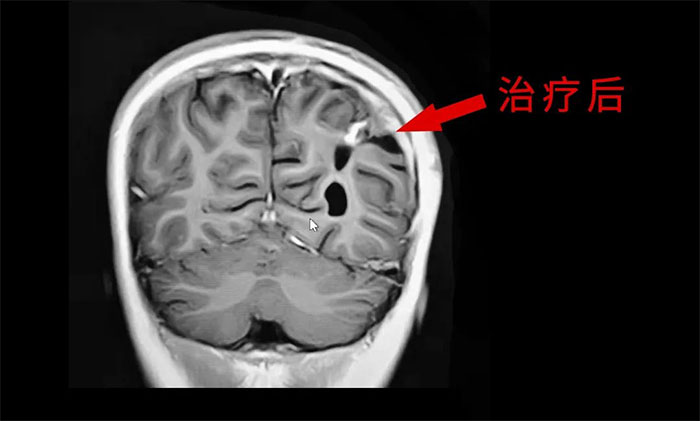

目前,腦膠質(zhì)瘤的治療方面,倡導(dǎo)MDT多學(xué)科診治,神經(jīng)外科、影像科、放射治療科、腫瘤科、病理科和康復(fù)科等多學(xué)科合作,遵循循證醫(yī)學(xué)原則,優(yōu)化和規(guī)范治療方案,采取個體化綜合治療,以期達(dá)到最大治療效益,盡可能延長患者的無進(jìn)展生存期(PFS) 和總生存期(OS),提高生存質(zhì)量。

外科手術(shù)往往是膠質(zhì)瘤治療的第一步。手術(shù)原則是在最大范圍安全切除(maximal safe resection)腫瘤的同時,保護(hù)神經(jīng)功能區(qū)。以解除占位征象和緩解顱內(nèi)高壓癥狀;解除或緩解因腦膠質(zhì)瘤引發(fā)的相關(guān)癥狀;獲得病理組織和分子病理,明確診斷;降低腫瘤負(fù)荷,為后續(xù)綜合治療提供條件。

放、化療等亦是不可或缺的重要治療手段,高級別膠質(zhì)瘤術(shù)后選擇標(biāo)準(zhǔn)同步放、化療可以取得顯著的生存獲益。

于耀宇主任特別指出,隨著腦血管介入技術(shù)快速發(fā)展,腦膠質(zhì)瘤術(shù)后超選介入化療聯(lián)合同步放療的效用正逐漸為大家所認(rèn)識。超選介入化療,是利用微導(dǎo)管技術(shù)直接將藥物通過供血動脈,灌注到顱內(nèi)腫瘤組織區(qū)域,避免了傳統(tǒng)口服或靜脈注射藥物,要經(jīng)過全身代謝后才能到達(dá)腫瘤區(qū)域?蓽p輕全身毒性反應(yīng),延長化療藥在腫瘤內(nèi)的滯留時間,更好地殺傷腫瘤細(xì)胞。

最后,于耀宇主任表示,膠質(zhì)瘤固然兇險,但我們應(yīng)當(dāng)正確認(rèn)識疾病,不盲目悲觀,更不應(yīng)輕易放棄治療。隨著醫(yī)療技術(shù)水平和治療手段的不斷提高,膠質(zhì)瘤患者在接受規(guī)范的治療后,延長生存期已成為可能,大可不必“談瘤色變”。